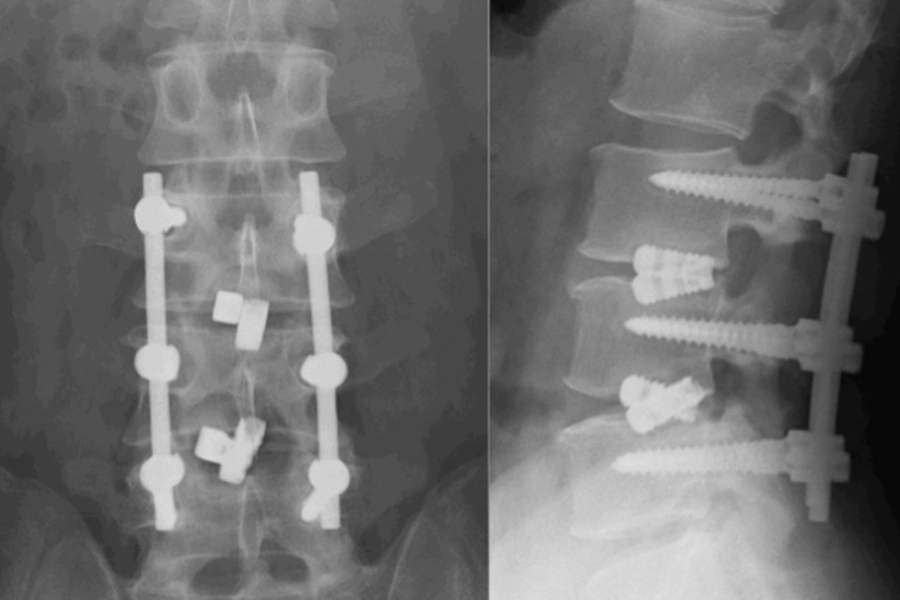

(A) Збільшені сагітальні та спрямовані наперед сили внаслідок використання увігнутого стрижня та коротшого, виступаючого (proud) розташування проміжного педикульного гвинта.

(B) Сили, спрямовані наперед, від конструкції «гвинт–стрижень» із реактивними силами, спрямованими назад, з боку переднього зв’язкового комплексу та періостальної манжетки, що сприяє зближенню уламків вибухового перелому та інтактної кісткової тканини.

(C) Міжуламкові рухи фрагментів при вибуховому переломі.